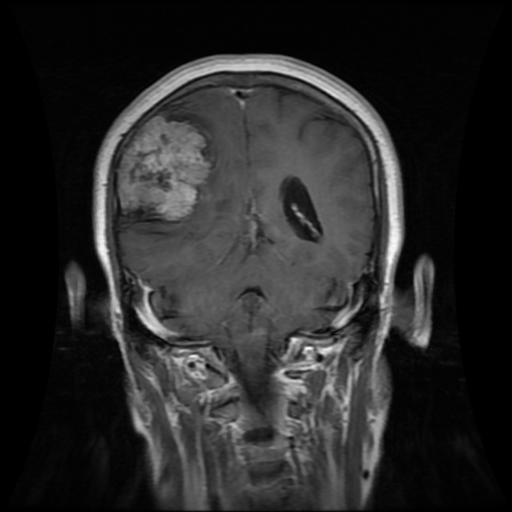

Figure 3: Samples of Pituitary segmentation across different imaging planes

Pituitary Tumors: Located at the base of the brain near critical structures like the optic chiasm, pituitary tumors demand careful delineation to avoid diagnostic errors. As shown in Figure 3, the segmentation accurately captures the tumor’s boundaries without encroaching on adjacent critical regions.